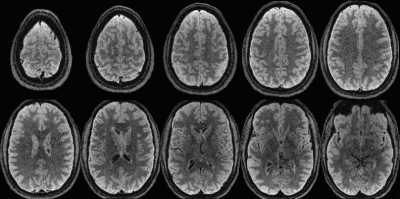

Figure 3: Raw images (no bias correction) of subject #1 at different axial locations for the TR = 2 s TurboYarn sequence.